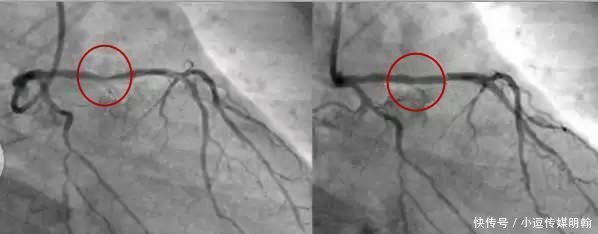

没错,这就是有效的疏通动脉血管的心脏支架!

598x302 - 20KB - JPEG